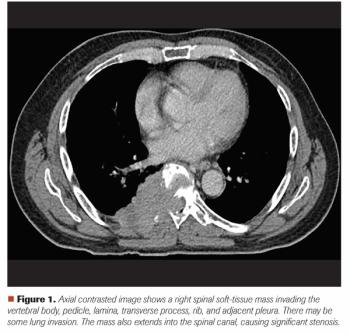

A 65-Year-Old Man With Back Pain and Imaging Findings of Spinal Cord Compression

ByMehmet Sitki Copur, MD,Scott Bell, MD, PhD, MPH,Paul Rodriguez, MD,Whitney Wedel, MD,Nicholas Lintel, MD,Thomas Zusag, MD,John L. Allen, MD Mehmet S. Copur, MD, and colleagues examine the case of a 65-year-old who presented with back pain and a large T8 spinal mass, leading to a diagnosis of multiple myeloma with spinal cord compromise.